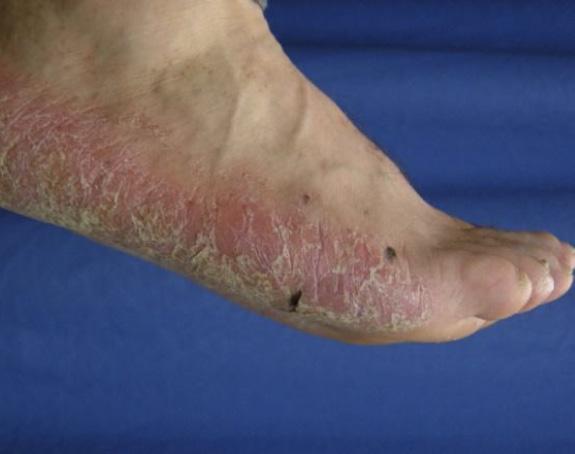

La Psoriasis en placa generalmente se manifiesta en cuero cabelludo, codos, rodillas y glúteos, pero puede envolver cualquier parte del cuerpo incluyendo las uñas, palmas y plantas, oídos y el área genital. Cuando la Psoriasis afecta las manos y los pies, puede producir dolor debido a fisuras en la piel. Además, la persona con Psoriasis palmar, frecuentemente se siente retraídas pues no se atreven estrecharle la mano a otra persona al saludarla. Fig 2.

Fig.2 Psoriasis palmoplantar Palabras Clave: Psoriasis, tratamientos biológicos